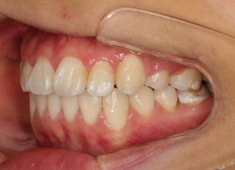

治療開始から11ヶ月後